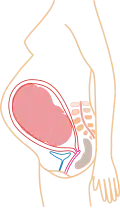

La grossesse, appelée aussi gestation humaine, est l'état d'une femme enceinte, c'est-à-dire portant un embryon ou un fœtus humain, en principe au sein de l'utérus, qui est dit gravide. En général, elle fait suite à un rapport sexuel, débute selon le point de vue à partir de la fécondation (fusion d'un ovule et d'un spermatozoïde) ou de la nidation (implantation de l'embryon dans l'utérus), et se déroule jusqu'à l'expulsion de l'organisme engendré. La durée moyenne de la fécondation à l'accouchement pour une grossesse unique est de 38 semaines et deux jours[1], soit un peu moins de neuf mois, une durée largement reprise dans la culture. Dans les faits, cette durée est variable selon les personnes et le déroulement de la grossesse. Ainsi, une grossesse normale dure entre 37 et 41 semaines d'aménorrhée (SA) ; on parlera alors de grossesse menée à terme. Pour une durée inférieure à 37 SA, on parle de prématurité et, pour une durée supérieure à 41 SA, on parle de postmaturité.

La grossesse s'accompagne de modifications importantes de l'organisme, que ce soit sur le plan physique, notamment au niveau de l'utérus, ou sur le plan psychique. Plusieurs pathologies peuvent survenir au cours de la grossesse, qu'elles soient spécifiques ou non. Certaines de ces pathologies, parfois sans conséquence en dehors de la grossesse, peuvent avoir un retentissement important sur l'embryon ou le fœtus. En conséquence, une adaptation du mode de vie et un suivi particulier sont conseillés pour la femme enceinte. La spécialité médicale concernée est l'obstétrique. La grossesse peut aussi avoir des conséquences culturelles, sociales ou économiques pour les parentes et parents, notamment dans le cas des grossesses à l'adolescence ou de grossesses non désirées.

Modifications physiques de l'organisme maternel